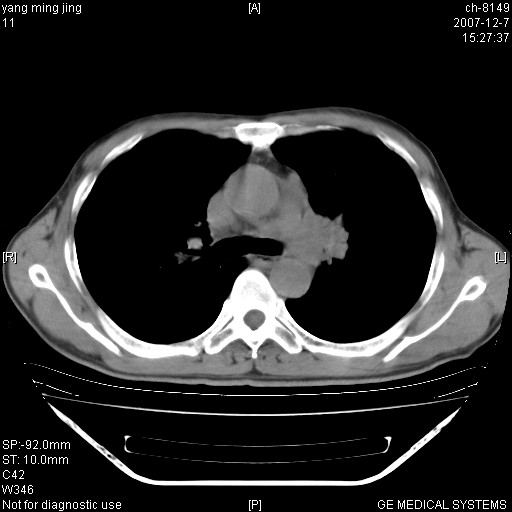

以下是引用zsl6918在2007-12-7 22:22:00的发言:[br]左肺上叶中心性肺癌并肺内及纵隔淋巴结转移,肝内转移。小细胞肺癌可能性大。

以下是引用狙击手在2007-12-8 11:03:00的发言:[br]考虑:左肺上叶中心性肺癌并肺内及纵隔淋巴结转移,肝内转移。